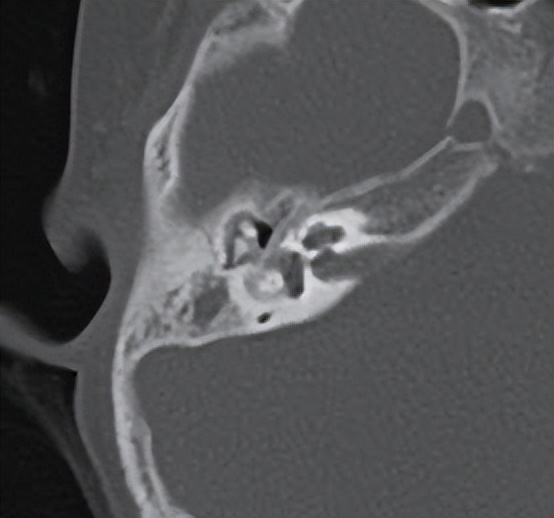

通过好大夫互联网医院预约好住院后,小尹和妈妈顺利入住了禅医耳鼻喉科。做完术前评估后,梅晓峰主任、郑立岗主任和耳鼻喉团队认真评估了小尹的病情,双侧重度粘连性中耳炎,右侧比左侧严重,这次建议做右侧,采用耳内镜微创技术,可以最大限度的保留所有的中耳结构,对孩子的一生都是非常有好处的。

手术由郑立岗主任亲自主刀,由于孩子的右侧鼓膜内陷得非常严重,手术的难度非常大,要从听骨链和鼓室内侧壁完整地剥离上皮组织,是一个非常精细的操作,没有十年的精细操作功夫是非常难成功完成的。郑主任在这方面有比较多的成功手术经验,所以整个的过程是非常顺利的,完整翻起了内陷的上皮组织。但孩子的砧镫关节术中看还是被内陷的上皮腐蚀断裂了,由于孩子比较小,郑主任并没有用人工听骨。而是采用了自体听骨对接的新技术,把断裂的听骨接在了一起。整个手术做了130分钟,非常的顺利。术后查房患者无明显的不适,无手术并发症。